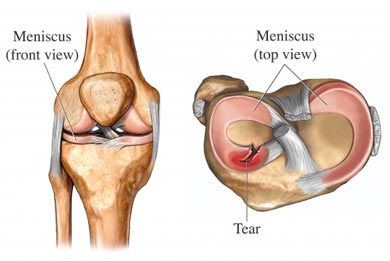

Типовий розрив меніска з вивихом типу «ручка лійки» на схемі і через артроскоп

Ознаки розриву меніска – раптовий колючий біль в коліні при певному русі, що супроводжується відчуттям заскоку, клацання, блокування; раптова поява обмежень у згинанні або розгинанні коліна; набряк в коліні. Для підтвердження діагнозу проводиться магнітно-резонансна томографія.